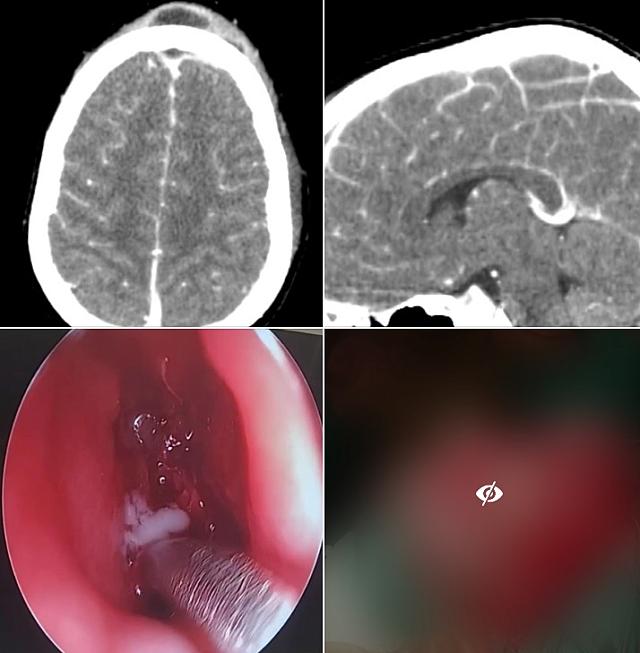

Ο κλινικός και απεικονιστικός έλεγχος ανέδειξαν βαριά μετωπιαία κολπίτιδα και οστεομυελίτιδα, ηθμοειδίτιδα, καθώς και συνοδό ενδοκρανιακό απόστημα.

Στο χειρουργείο, υπό γενική αναισθησία, παροχευτεύηθηκε επιτυχώς το πύο από το μετωπιαίο κόλπο και τις ηθμοειδείς, με ενδοσκοπική προσπέλαση. Ακολούθως, οι νευροχειρουργοί διενέργησαν ανοικτή κρανιοτομή και παροχέτευσαν το υποσκληρίδιο απόστημα του εγκεφάλου.

Η ανταπόκριση του μικρού ασθενούς ήταν εντυπωσιακή. Μετά από σύντομη παραμονή στη ΜΕΘ παίδων, βρίσκεται πλέον, σαφώς βελτιωμένος, στην παιδιατρική κλινική.